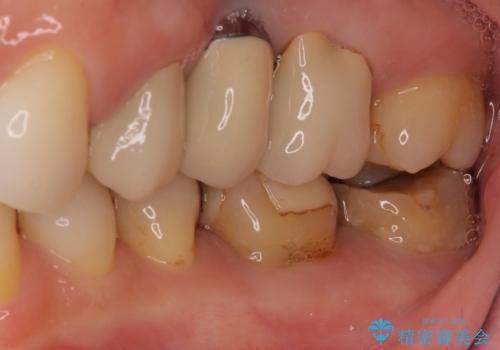

- 奥歯にものが挟まったり引っかかったりすることを気にして来院された患者様です。

詰め物と歯に隙間ができており、既に根管治療をされた歯であったため、フルジルコニアクラウンにて補綴治療をすることとしました。